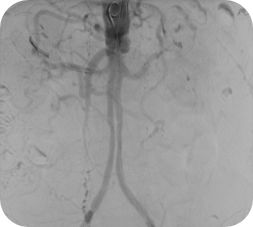

Vessel ASSIST für periphere Verfahren

Bei peripheren, chronischen Komplettverschlüssen (CTO) bietet die Vessel ASSIST-Lösung eine intuitive und genaue Lösung, die Sie bei der Planung und Führung komplexer endovaskulärer CTO-Eingriffe unterstützt. 1

Die automatische Segmentierung von Knochen und Gefäßen und die Mittellinienverfolgung durch den Gefäßverschluss ermöglichen eine schnelle Planung anhand von präoperativen CT- oder MR-Bildern. Durch diese Kombination präoperativer CT- oder MR-Bilder mit Mittellinienverfolgung und Durchleuchtung in Echtzeit können Spezialisten außerordentlich gut sehen, wo die Rekanalisation vorgenommen werden muss und wo sich die Einstichstelle befindet, ohne die Kontrastmittelmenge erhöhen zu müssen.